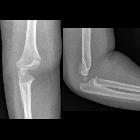

Supracondylar humeral fractures, often simply referred to as supracondylar fractures, are a classic pediatric injury which requires vigilance as imaging findings can be subtle.

Typically supracondylar fractures occur as a result of a fall on a hyper-extended elbow. They result in an extra-articular fracture line, and (when displaced) posterior displacement of the distal component.

Plain radiograph

Lateral and AP radiographs are usually sufficient, and in many instances demonstrate an obvious fracture. Often, however, no fracture line can be identified. In such cases assessing for indirect signs is essential:

- anterior fat pad sign (sail sign): the anterior fat pad is elevated by a joint effusion and appears as a lucent triangle on the lateral projection

- posterior fat pad sign

- anterior humeral line should intersect the middle third of the capitellum in most children although, in children under 4, the anterior humeral line may pass through the anterior third without injury